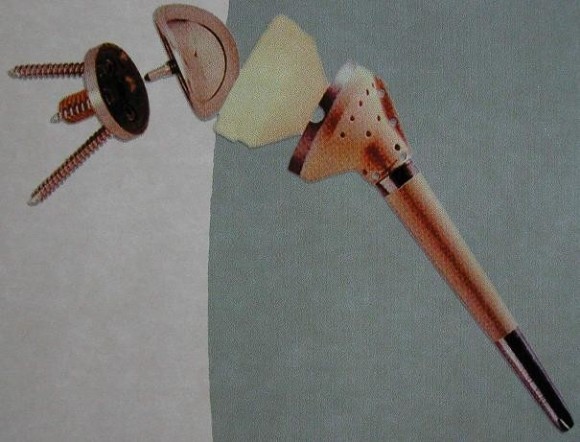

Like the knee and hip, the used up cartilaginous articular surface of the shoulder and the underlying, mostly already dead bone is removed sparingly, and replaced by a metal implant to the humeral head (hemiarthroplasty) and eventually additionally by an acetabulum implant (total hip). Meanwhile, the fourth generation of shoulder prostheses is already on the market. This new prosthesis design allows a largely anatomical reconstruction of the joint. Special types of prostheses are available even for completely missing or not reconstructable muscle cuffs.

Below: Special prosthesis